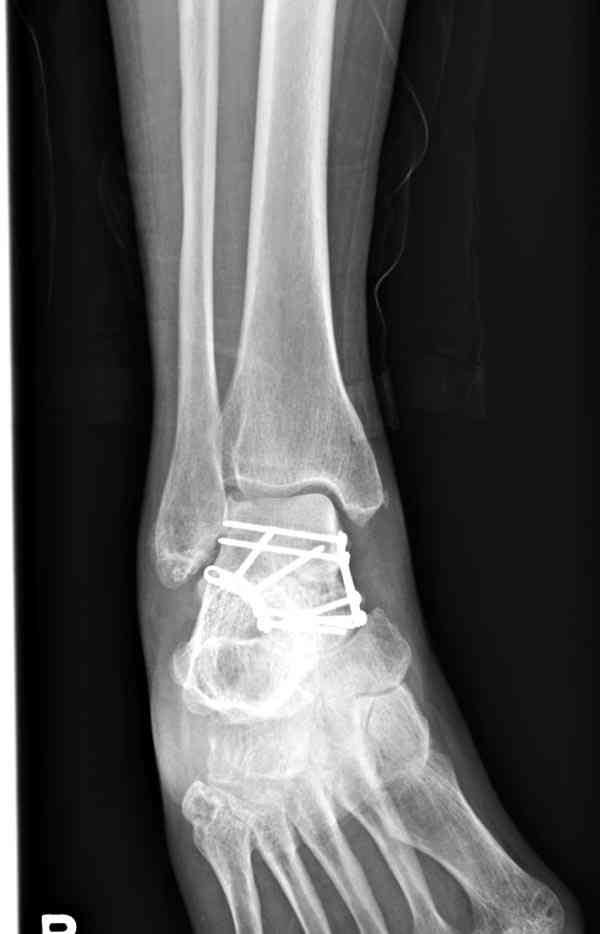

При в первом типе придерживаемся закрытой репозиции, а у всех остальных в зависимости от смещения предпочитаем открытую репозицию, фиксация шурупами или пластиной. Пластина 2.4 мм более предпочтительна для удержания мелких костных осколков.

В вашем случае доступ через перелом медиальной лодыжки, обычный доступ через остеотомии лодыжки, где имеется возможность прямой репозиции тарана, после фиксации шурупами, лодыжки фиксируются обычным 2х лодыжечным методом.

Случай с множественным оскольчатым переломом тарана оперированный из двойного доступа.

Через 2 мес.: